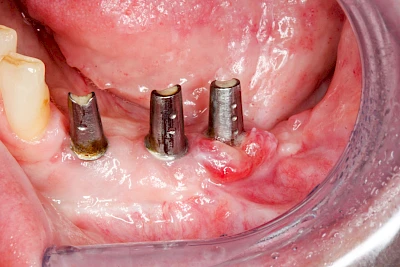

Bei Implantaten – also operativ eingebrachten künstlichen Zahnwurzeln – kann der Körper die Bakterien auch nicht so gut abwehren. Hier spricht man im Fall einer Entzündung von einer Peri-Implantitis, also einer Entzündung um das Implantat herum.

Ist zunächst nur das Zahnfleisch von der Entzündung betroffen, spricht man von Gingivitis. Später, wenn auch der Knochen um die Zähne herum entzündet ist, spricht man von einer Parodontitis. Bei der Parodontitis wird der Knochen nach und nach abgebaut und das Zahnfleisch zieht sich zurück. Die Zahnhälse und Zahnwurzeloberflächen liegen mehr und mehr frei. Die Zähne werden zunehmend lockerer und fallen schließlich aus.